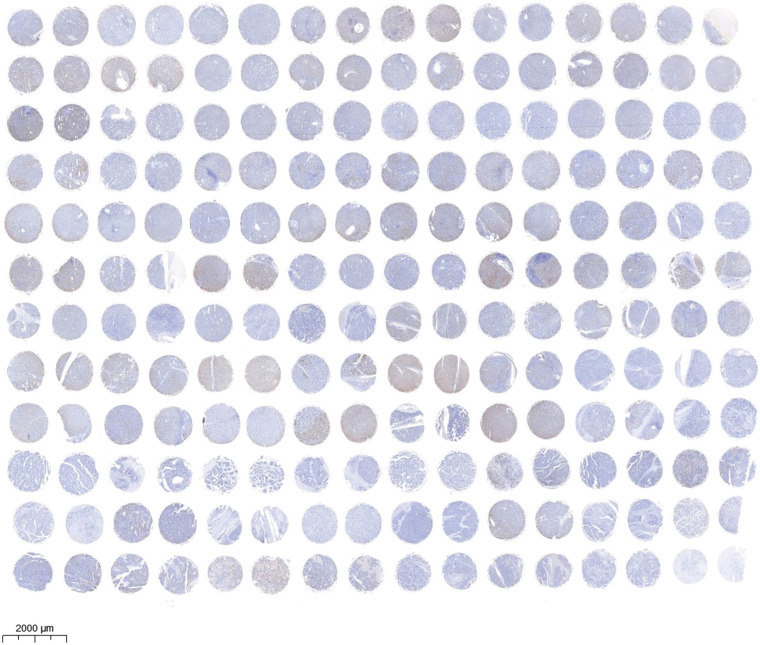

Tissue array and immunohistochemistry (IHC)

The human liver tissue array (DC-Liv00009) was obtained from Alenabio, Inc. (Xi’an, China) and analyzed according to the manufacturer’s instructions. In summary, the tissue sections of the human liver tissue array or the mice tumor tissues were deparaffinized and rehydrated and then endogenous tissue peroxides were quenched. The sections incubated with 3% H2O2 #88597 (Sigma, Billerica, MA, USA) for 10 min and then blocked with 1% BSA for 20 min. The sections were then incubated overnight at 4°C with corresponding primary antibodies (1:1000). Subsequently, the sections were incubated at 37°C for 1 h with HRP-labeled secondary antibodies (1:1000), and then were stained with DAB reagents #D8001 (Sigma, Billerica, MA, USA) and counterstained with hematoxylin. The tissues were examined and imaged with the microscope at 400× magnification. The IHC stains were assessed by figuring an H-score, and H-score greater than 6 indicates high EMP2 protein expression while H-score less than 6 indicates low EMP2 protein expression.

Immunohistochemical staining was performed to evaluate the expression level of EMP2 protein in liver disease tissue microarrays. HCC tissue exhibited a significantly higher positive rate of EMP2 compared to normal liver tissue. Furthermore, in HCC tissue, a higher level of EMP2 protein expression was associated with greater morphological heterogeneity and higher malignancy. The EMP2 positive stained ratio were around 20% in the normal liver and chronic hepatitis tissues, and over half of HCC tissue with high EMP2 staining (Figs. 4A and A1, Table A2). EMP2 was primarily localized in the cytoplasm, with minimal nuclear staining observed. The experimental results demonstrated an increasing trend in EMP2 protein expression as liver disease progressed from inflammation to liver cirrhosis and ultimately to HCC. Moreover, the expression level of EMP2 protein in HCC tissue positively correlated with the malignancy grade, indicating a significant role of EMP2 in the progression of liver diseases. To further validate these findings, six pairs of HCC tissues and matched adjacent normal liver tissues were collected. In five out of the six tissue samples, HCC tissues exhibited significantly higher levels of EMP2 expression compared to adjacent liver tissues. However, in one pair of tissues, the difference in EMP2 protein expression between HCC tissues and adjacent liver tissues was not sound (Figs. 4B–4D). In addition, the level of EMP2 protein expression was assessed in various liver or liver cancer cell lines. EMP2 protein expression was low in the normal liver epithelial cell line THLE-3. In contrast, the level of EMP2 protein expression was relatively high in five HCC cell lines (including Hep-3B, HepG2, SNU182, Huh-7, and SK-Hep-1).